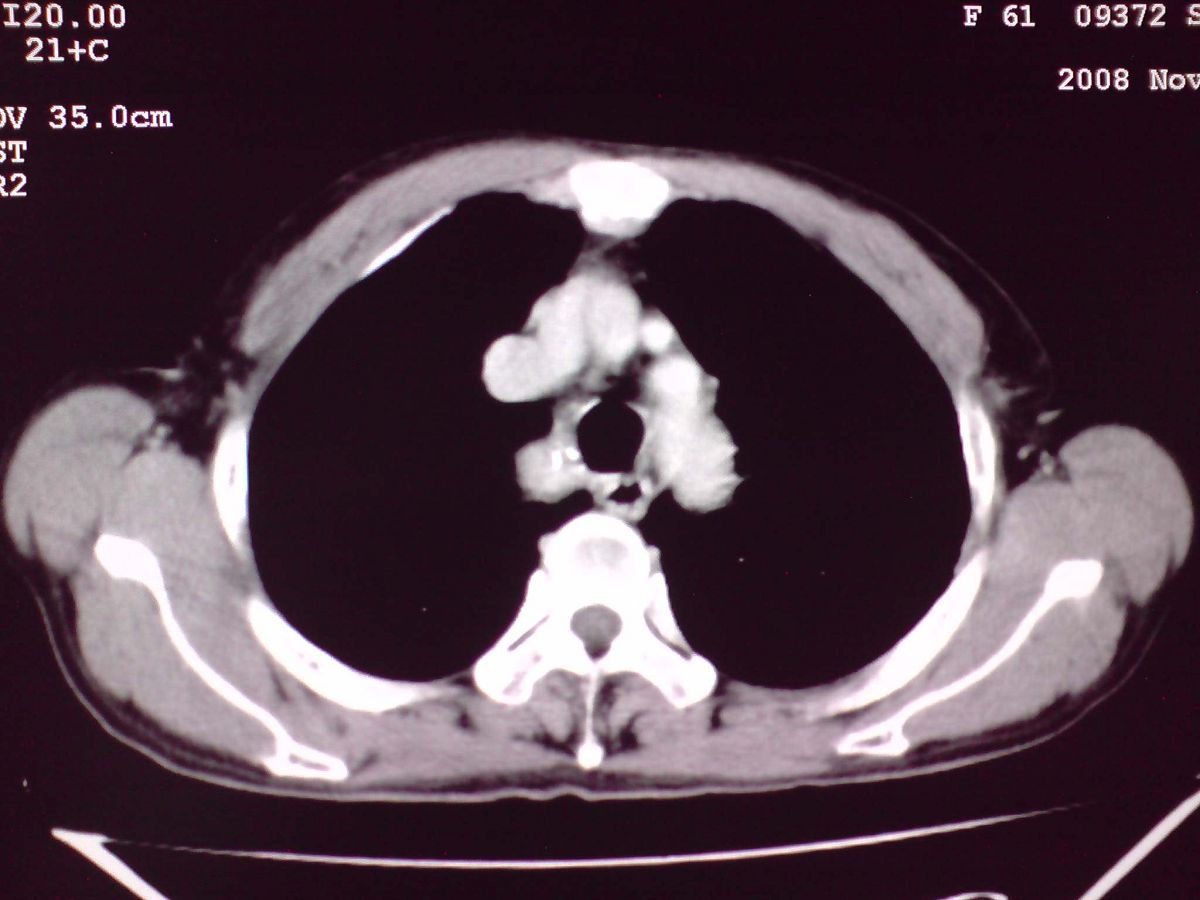

患者女性,65岁,无明显不适,甲状腺功能无异常

双侧甲状腺肿大,向下部分突入胸腔,双侧甲状腺内密度不均,可见结节状低密度影,并见散在斑点状钙化,增强后病灶实性部分强化明显,气管受压稍变窄左移。

考虑:双侧甲状腺腺瘤可能,不除外甲状腺癌。

胸内甲状腺,双侧结节状甲状腺肿伴右侧甲状腺腺瘤。

甲状腺左右叶增大,并向下突入胸腔内,其内可见多发条片状钙化影及囊性低密度影,邻近组织及血管无浸润、包埋征像,双侧结节性甲状腺肿伴右侧甲状腺腺瘤形成可能性大,甲状腺癌待排;因病人就要手术,期待结果。

我们的诊断和大家一致,但我们地区的上级医院考虑右纵隔是另外一种病变